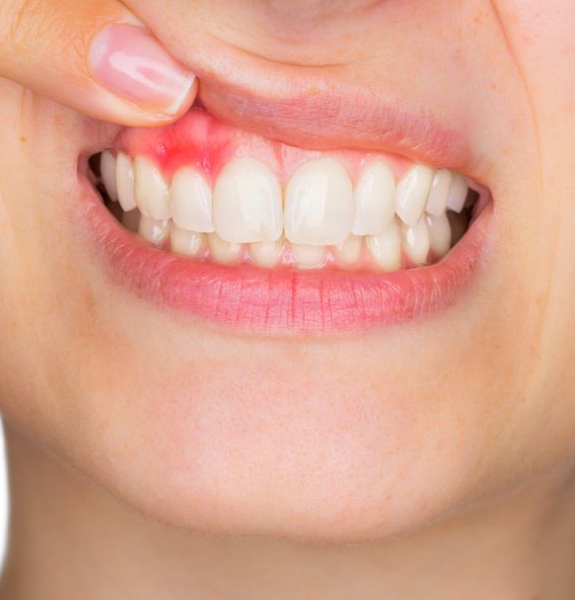

A gengivite crônica é a inflamação da gengiva que, se não tratada, pode evoluir. Ela acontece pelo acúmulo de placa bacteriana. Isso causa vermelhidão, inchaço e até sangramento ao escovar os dentes. Ignorar pode levar a problemas mais sérios, como a periodontite, que afeta os ossos que sustentam os dentes.

A gengivite crônica pode parecer uma coisa pequena, mas se não for tratada, ela pode se agravar e trazer outros problemas. É aquela inflamação persistente que deixa a gengiva inchada e às vezes sangrando. O principal culpado? Acúmulo de placa bacteriana. Pois é, aquela sujeirinha que não sai com uma escovação básica. Precisamos ser mais eficientes na limpeza diária.

Se você notar que sua gengiva está sempre vermelha, sensível ou até mesmo recuando, pode ser gengivite crônica. Não ignore esses sinais! A boa notícia é que, na maioria das vezes, com os cuidados certos em casa e, claro, acompanhamento do dentista, a situação melhora muito. Ele poderá te orientar sobre os produtos e técnicas mais adequados para o seu caso.

A gengivite crônica se caracteriza por uma inflamação persistente na gengiva, que fica vermelha, inchada e pode até sangrar com facilidade. Muitas vezes, a causa é o acúmulo de placa bacteriana que não foi removida corretamente com a escovação e o fio dental. Quando ela se torna crônica, os cuidados caseiros podem não ser suficientes para reverter o quadro, e a ajuda profissional se torna indispensável.